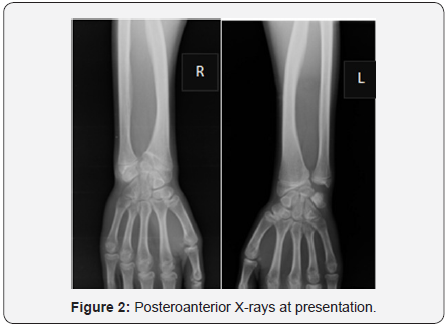

The postero anterior wrist X-rays (Figure 2) showed typical Madelung deformity changes on both wrists: shortening of the radius compared to the ulna, radially curved radius, a mismatch of the distal radioulnar joint and a triangular-shaped carpus. The lateral projection (Figure 3) demonstrated predominant changes on the right wrist: dorsal dislocation of the ulnar and an exaggerated volar tilt of the radioulnar joint in a way that made palmar carpal displacement and an anterior translation of the hand and the wrist. It was performed on the right side ametaphysic triplane osteotomy of the distal radius with Vicker’s ligament release, and an ulnar shortening osteotomy with plate fixation (Figure 4). There was no intra and postoperative complications.